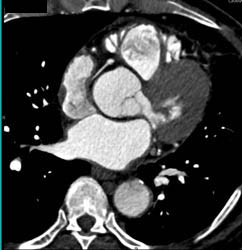

Enlarged Left Ventricle